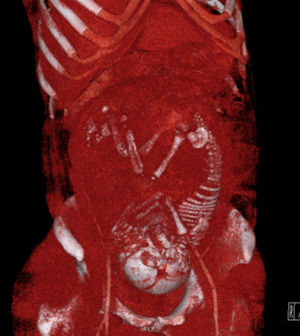

تصوير بالرنين المغناطيسي

التصوير بالرنين المغناطيسي، بدون وسط تباين في التصوير بالرنين المغناطيسي، لا يرتبط بأي خطر على الأم أو الجنين، وإلى جانب تخطيط الصدى الطبي هو الأسلوب المفضل للتصوير الطبي في الحمل.[1]

يستخدم التصوير بالرنين المغناطيسي عادة في النساء الحوامل المصابات بالألم البطني و / أو الألم الحوضي، أو في الاضطرابات العصبية المشتبه فيها، وأمراض المشيمة، والأورام، والعدوى، و / أو الأمراض القلبية الوعائية.[3] تعطي معايير الاستخدام المناسبة من قبل الكلية الأمريكية للأشعة تصنيف ≥7